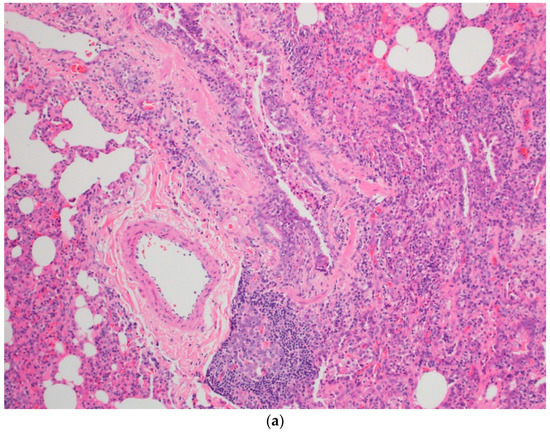

The child’s symptoms continued to worsen with progressive dyspnea and dry cough, and the decision was made to undergo an open lung biopsy with histopathology findings suggestive of acute hypersensitivity pneumonitis (HP) (Figure 3a,b). All pigeons were removed from the household, and lifetime avoidance of exposure to pigeons was recommended. He was further treated with pulse steroid therapy (30 mg/kg/day) for 3 days with the plan to give 3–6 cycles of monthly pulse steroids with follow up in an outpatient clinic.

Figure 3.

Sections show wedge lung biopsy characterized by patchy inflammatory process. The inflammation is bronchiolocentric (a) with significant extension into the interstitium consisting of sheets of lymphocytes, plasma cells, foamy macrophages, and rare eosinophils as well as neutrophils (b). No definitive granulomas, desquamation, vasculitis, significant eosinophilic infiltrate, Langerhans’ cells, or fibrosis are seen. Special stains for fungi, acid-fast organisms, and viral inclusions are negative.

The pathophysiology of HP is complex and not well understood. Numerous organic and inorganic antigens can cause immune dysregulation, leading to an immune-related antigen–antibody response (IgG against the offending antigen) [2,3,4]. Others have suggested underlying genetic factors that may contribute to the development of BFL [1]. Pathologically, finding of lymphocytic plasma cell infiltration and foamy macrophages were found in our patient’s histopathological lung biopsy, which are distinguishable parenchymal changes that occur during the acute/subacute phase of an illness. No definitive granulomas were seen (Figure 3a,b) [4].